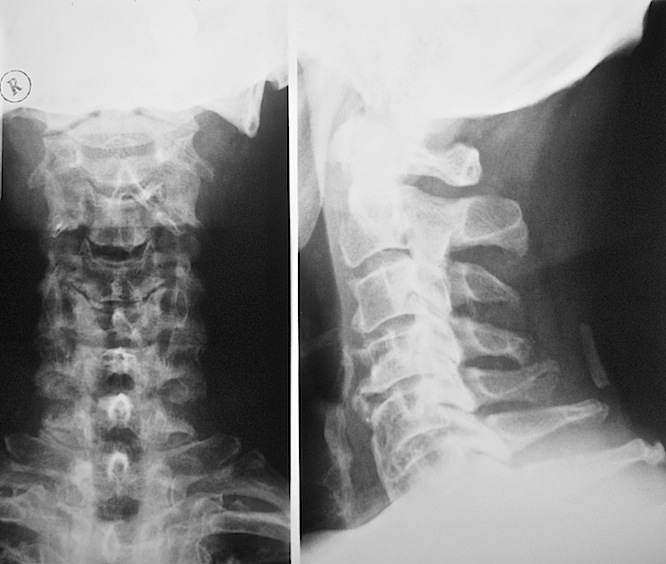

Диагностика

Диагностика — важный этап при подозрении на хлыстовую травму шеи. Она помогает оценить тяжесть и тип повреждений.

Пациенту необходимо пройти следующие исследования:

- рентгенография — для оценки состояния шейных позвонков;